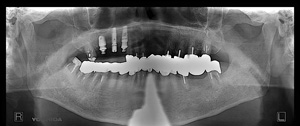

H.F‚³‚ñ @64Î —«@Žå•w@Žèp“ú  ‚Q‚O‚P‚P”N ‚PŒŽ‚Q‚P“úi‹àj   ㉺Š{ƒm[ƒxƒ‹ƒKƒCƒhŽg—p@ Ö¬“à’ÁÖ@•¹—p@

@@@@@ãŠ{@@ALL on ‚U @’x‰„‰×d@@‚h‚oƒCƒ“ƒvƒ‰ƒ“ƒg ‚T–{–„“üƒvƒƒrƒZƒbƒg

@@@  @@@@@@”16@Rp‚Œ Tapered Groovy Wp ~ 13 mm@@ @ ”14 Nb  Speedy Groovy Rp ~ 11.5 mm@@@@”12@Bmk MK‡V Rp 3.75 ~ 11.5 mm

@@@@ @@@@@ ”22@Bmk MK‡V Rp3.75  ~ 11.5 mm@@         ”24 Nb Speedy Groovy Rp  ~ 11.5 mm@@@@”2‚U Rpl  Tapered Groovy Wp  ~  13 mm@@

@@@@‰ºŠ{@@ALL on ‚U @‘¦Žž‰×d

@@@@ @@@@@ ”36 Rp‚Œ Tapered Groovy Rp ~ 10 mm  @  ”34 Rp‚Œ Tapered Rp ~ 10 mm            ”32 Rpl Tapered Np ~ 13 mm@

@@@@ @@@@@ ”42 Rp‚Œ Tapered Np ~ 13 mm@ @@ @      ”44 Bmk MK‡V Rp3.75 ~ 10 mm  @     ”4‚U Rpl Taperde Grovy Rp

~ 10 mm